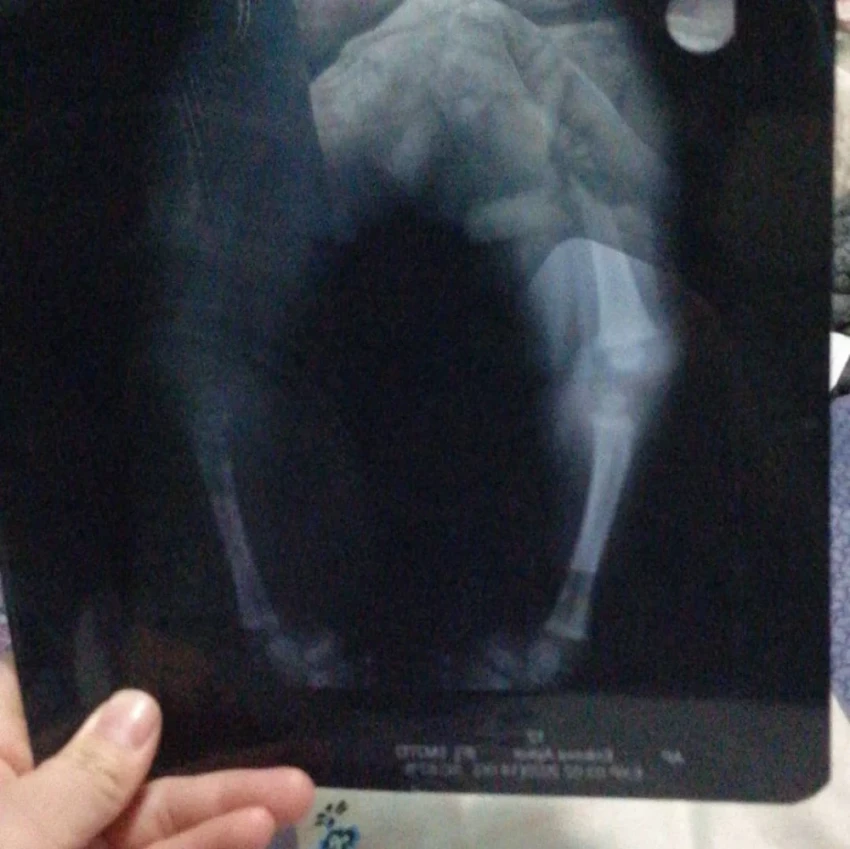

Айкол уже перенесла две операции в Бишкеке, направленные на исправление двусторонней деформации голеностопного сустава, но, к сожалению, результаты оказались неудовлетворительными.

"Я узнала, что за границей есть возможность провести более сложную и эффективную операцию. Начала собирать информацию и обратилась к врачам в Турции, которые уверили, что в нашем случае можно исправить косолапость. Стоимость операции составляет $25 тыс. Но я не знаю, как смогу собрать такую сумму", - говорит Бегимай.